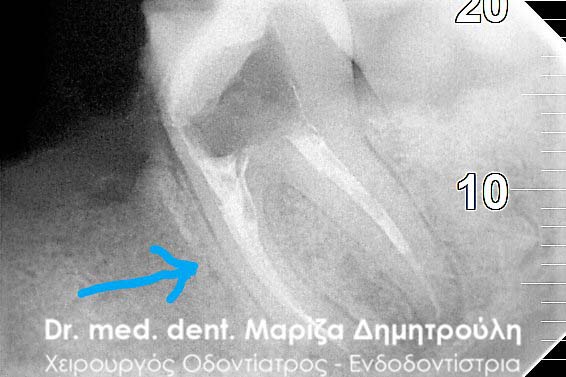

Clinical photo after the preparation of root canals of the tooth